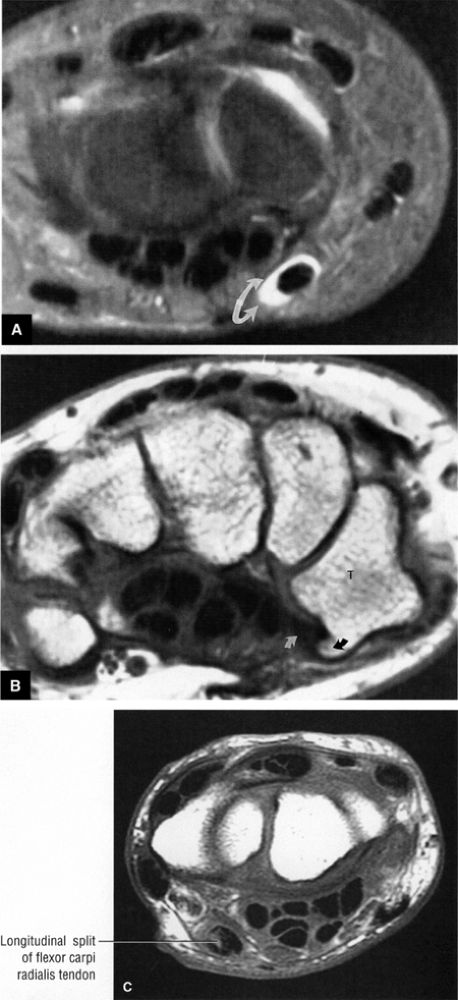

FIGURE 10.4 ● FLEXOR CARPI RADIALIS The flexor carpi radialis lies radial to the palmaris longus and ulnar to the pronator teres throughout its course. It contributes to flexion and abduction of the wrist. Distal flexor carpi radialis tendon rupture, usually occurring after a fall on the outstretched hand, can clinically mimic a scaphoid fracture.

|